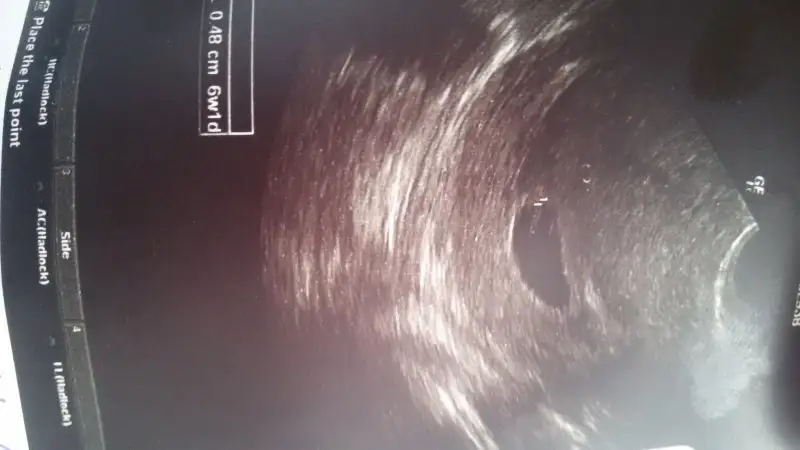

Merhaba kızlar... 6 haftalik vajinal USG Resmimi yüklüyorum bizde yorum yaparmisiniz rica etsem.